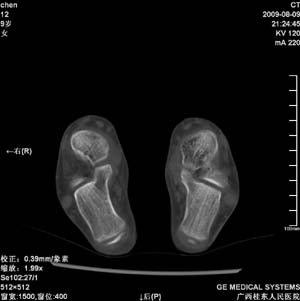

标题: PED2867:右侧内踝肿胀,骨质改变,请各位老师会诊 [打印本页]

标题: PED2867:右侧内踝肿胀,骨质改变,请各位老师会诊

九岁小朋友,近期左侧内踝疼痛,局部肿胀,平时无特殊,近期经常溜干冰

对不起,是右侧内踝肿胀

双踝关节骨质及发育未见异常。

左侧内踝密度增高,请结合临床!